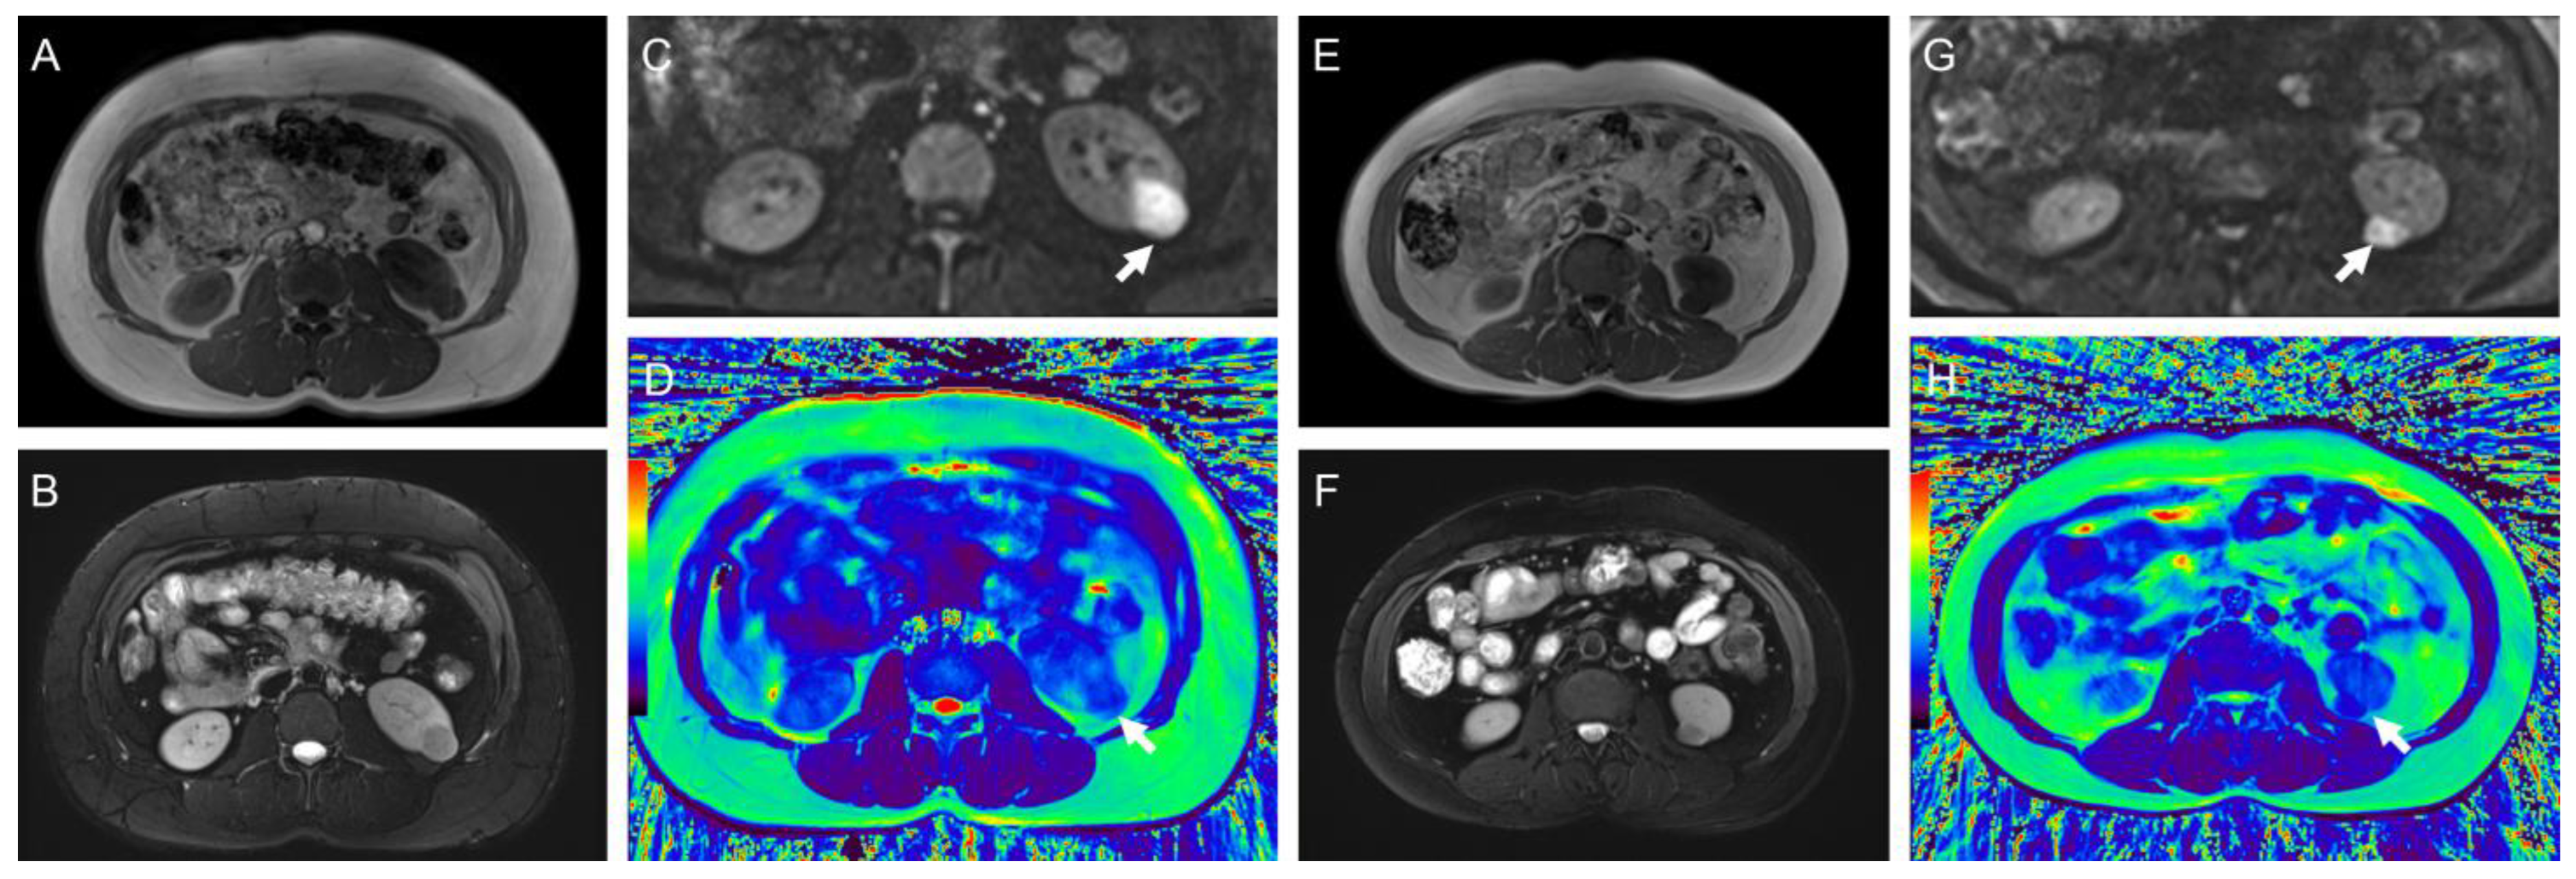

Figure 3. (AD) Representative images of a 65-year-old woman with WHO/ISUP II ccRCC in the right kidney (arrow): (A) axial T1-weighted image; (B) T2-weighted image; (C) diffusion-weighted images (b = 800 s/mm2); (D) radial TSE T2 map. The mean ADC and T2 values of the tumor were 1.51 mm2/s and 141.4 ms, respectively. (EH) Representative images of a 51-year-old man with WHO/ISUP III ccRCC with tumor necrosis in the left kidney (arrow): (E) axial T1-weighted image; (F) T2-weighted image; (G) diffusion-weighted images (b = 800 s/mm2); (H) radial TSE T2 map. The mean ADC and T2 values of the tumor were 1.11 mm2/s and 85.9 ms, respectively. The color bar in the pseudocolor images (D and H) represents T2 values, which gradually increase from black to red.

The typical multiparameter MR images of different pathological types and WHO/ISUP grades are illustrated in Figure 3 and Figure 4, and the distribution of T2 and ADC values is provided in Table 3 and Figure 5.